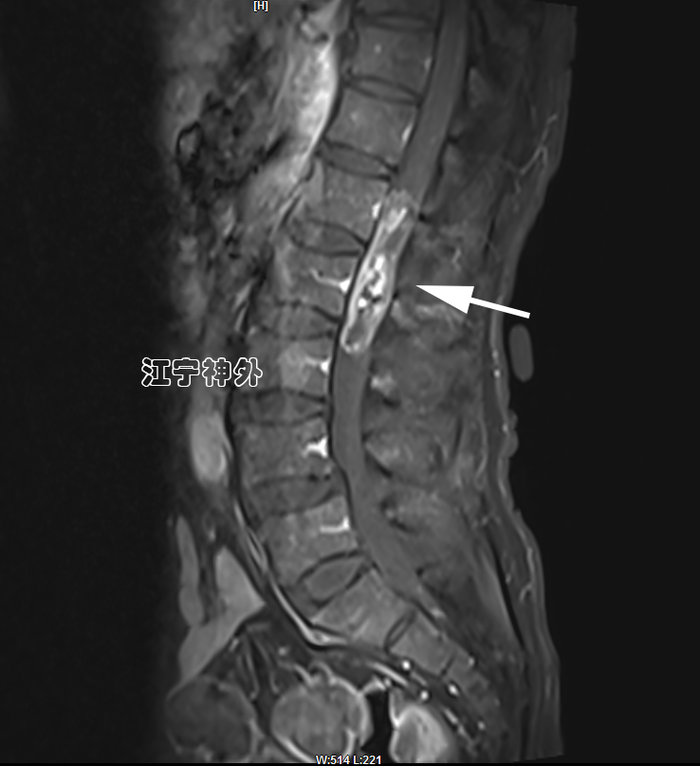

病例2:患者老年男性,因记忆力下降、行走不稳、经常跌倒、有时尿失禁来院,从症状来看,非常符合正常颅压脑积水的表现,而且CT上也确实存在脑室增大,因此就诊神经外科郑学胜主任门诊,并收治入院。然而,术前检查常规做腰穿时,发现脑脊液是草黄色的,压力也很低,提示椎管内存在梗阻性病变。于是,郑主任团队予以全脊柱增强磁共振检查,发现腰1-2水平巨大椎管肿瘤,很显然,上述行走不稳、跌倒、尿失禁等症状是椎管肿瘤引起的。

郑主任阅片发现,从横断面来看,肿瘤几乎占据了椎管全径,正常的脊髓圆锥和神经根已不可辨认,很难说是髓外硬膜下病变还是髓内病变。结合病程很长,脑脊液循环已完全阻断,推测肿瘤与脊髓圆锥、马尾神经根之间,以及肿瘤与硬脊膜之间很可能有明显粘连,所以手术难度较大,手术风险高。

经过充分的术前准备,郑学胜团队于2月16日在术中电生理监测下实施椎管肿瘤切除术;结果手术难度比预估的还要更大,因为不仅肿瘤质地很硬、血供丰富,而且肿瘤位于脊髓圆锥和神经根的腹侧,手术只能在圆锥和神经根的间隙里操作,肿瘤的腹侧又与硬脊膜严重粘连;郑学胜团队经过近6小时的手术,终于将肿瘤完整全切,并且脊髓圆锥和神经根保护良好。

术后磁共振显示,肿瘤无任何残留,脊髓圆锥和神经根恢复正常形态,术后大小便功能、下肢运动恢复正常。术后病理提示:神经鞘瘤伴出血。